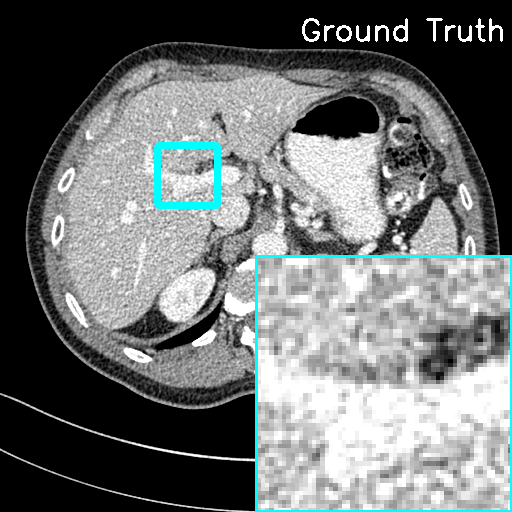

(ii) Domain-shift cases. In this study, Clinical LDCT dataset is selected as the testing set, while the AAPM Mayo Clinic dataset still remains as the training set for our model. Although the imaging operators of the training and testing sets remain the same, the CT images originate from different scanners. For comparison, we applied the traditional FBP algorithm directly to the Clinical LDCT dataset to obtain the reconstruction results. Fig. 10 shows the representative reconstructions with lesions using different methods. It can be seen that the proposed F-LInFBP and L-LInFBP methods achieve higher fidelity reconstructions with clear tissue depiction, i.e., better preserving lesion details. Moreover, subjective assessments from experienced radiologists are also conduced to evaluate the potential clinical application. Table 6 lists the average scores, indicating the potential application of the proposed LInFBP in clinical settings. These results highlight the reliability of the proposed LInFBP against variations in imaging operators and domain shifts.